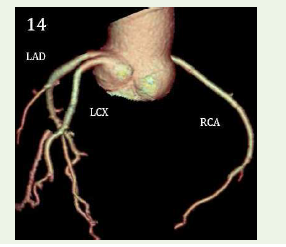

Case 5: A 48-year-old female with chest pain for 2 days, normal echocardiography, mildly positive for inducible ischemia in TMT with hypercholesterolemia demonstrated an anomalous separate origin of Left anterior descending and left circumex artery from left coronary sinus.

Figure 14:Maximum intensity projection reconstruction & 3D volume

rendered reformation shows an anomalous separate origin of Left anterior

descending & left circumflex artery from left coronary sinus.